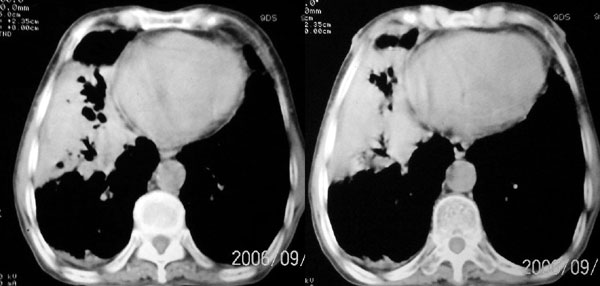

f 76 间断咳嗽 咳痰1年余 发热不明显 身体削瘦

征象:

1、右肺中叶近肺门区可见一空洞样病灶,内壁不规则,有与邻近支气管相通的征象,其外侧大片肺组织软组织状实变,余肺可见散在点、片絮状密度增高影,肺纹理可见明显增粗及串珠样改变;

2、纵隔气管前、隆突下、内乳组、心右前间隙以及右侧腋窝内均可见肿大的淋巴结节;

3、右侧胸膜增厚粘连,胸腔少量积液征像;

4、其它征像略。

诊断意见:

1、右侧中央型(空洞性)肺癌并双肺受累(包括转移、阻塞性炎症、癌性淋巴管炎);纵隔、右侧腋窝内淋巴结肿大、转移;右侧胸膜增厚粘连,胸腔少量积液;

2、双上肺陈旧性结核。

3、慢性支气管炎、肺气肿。